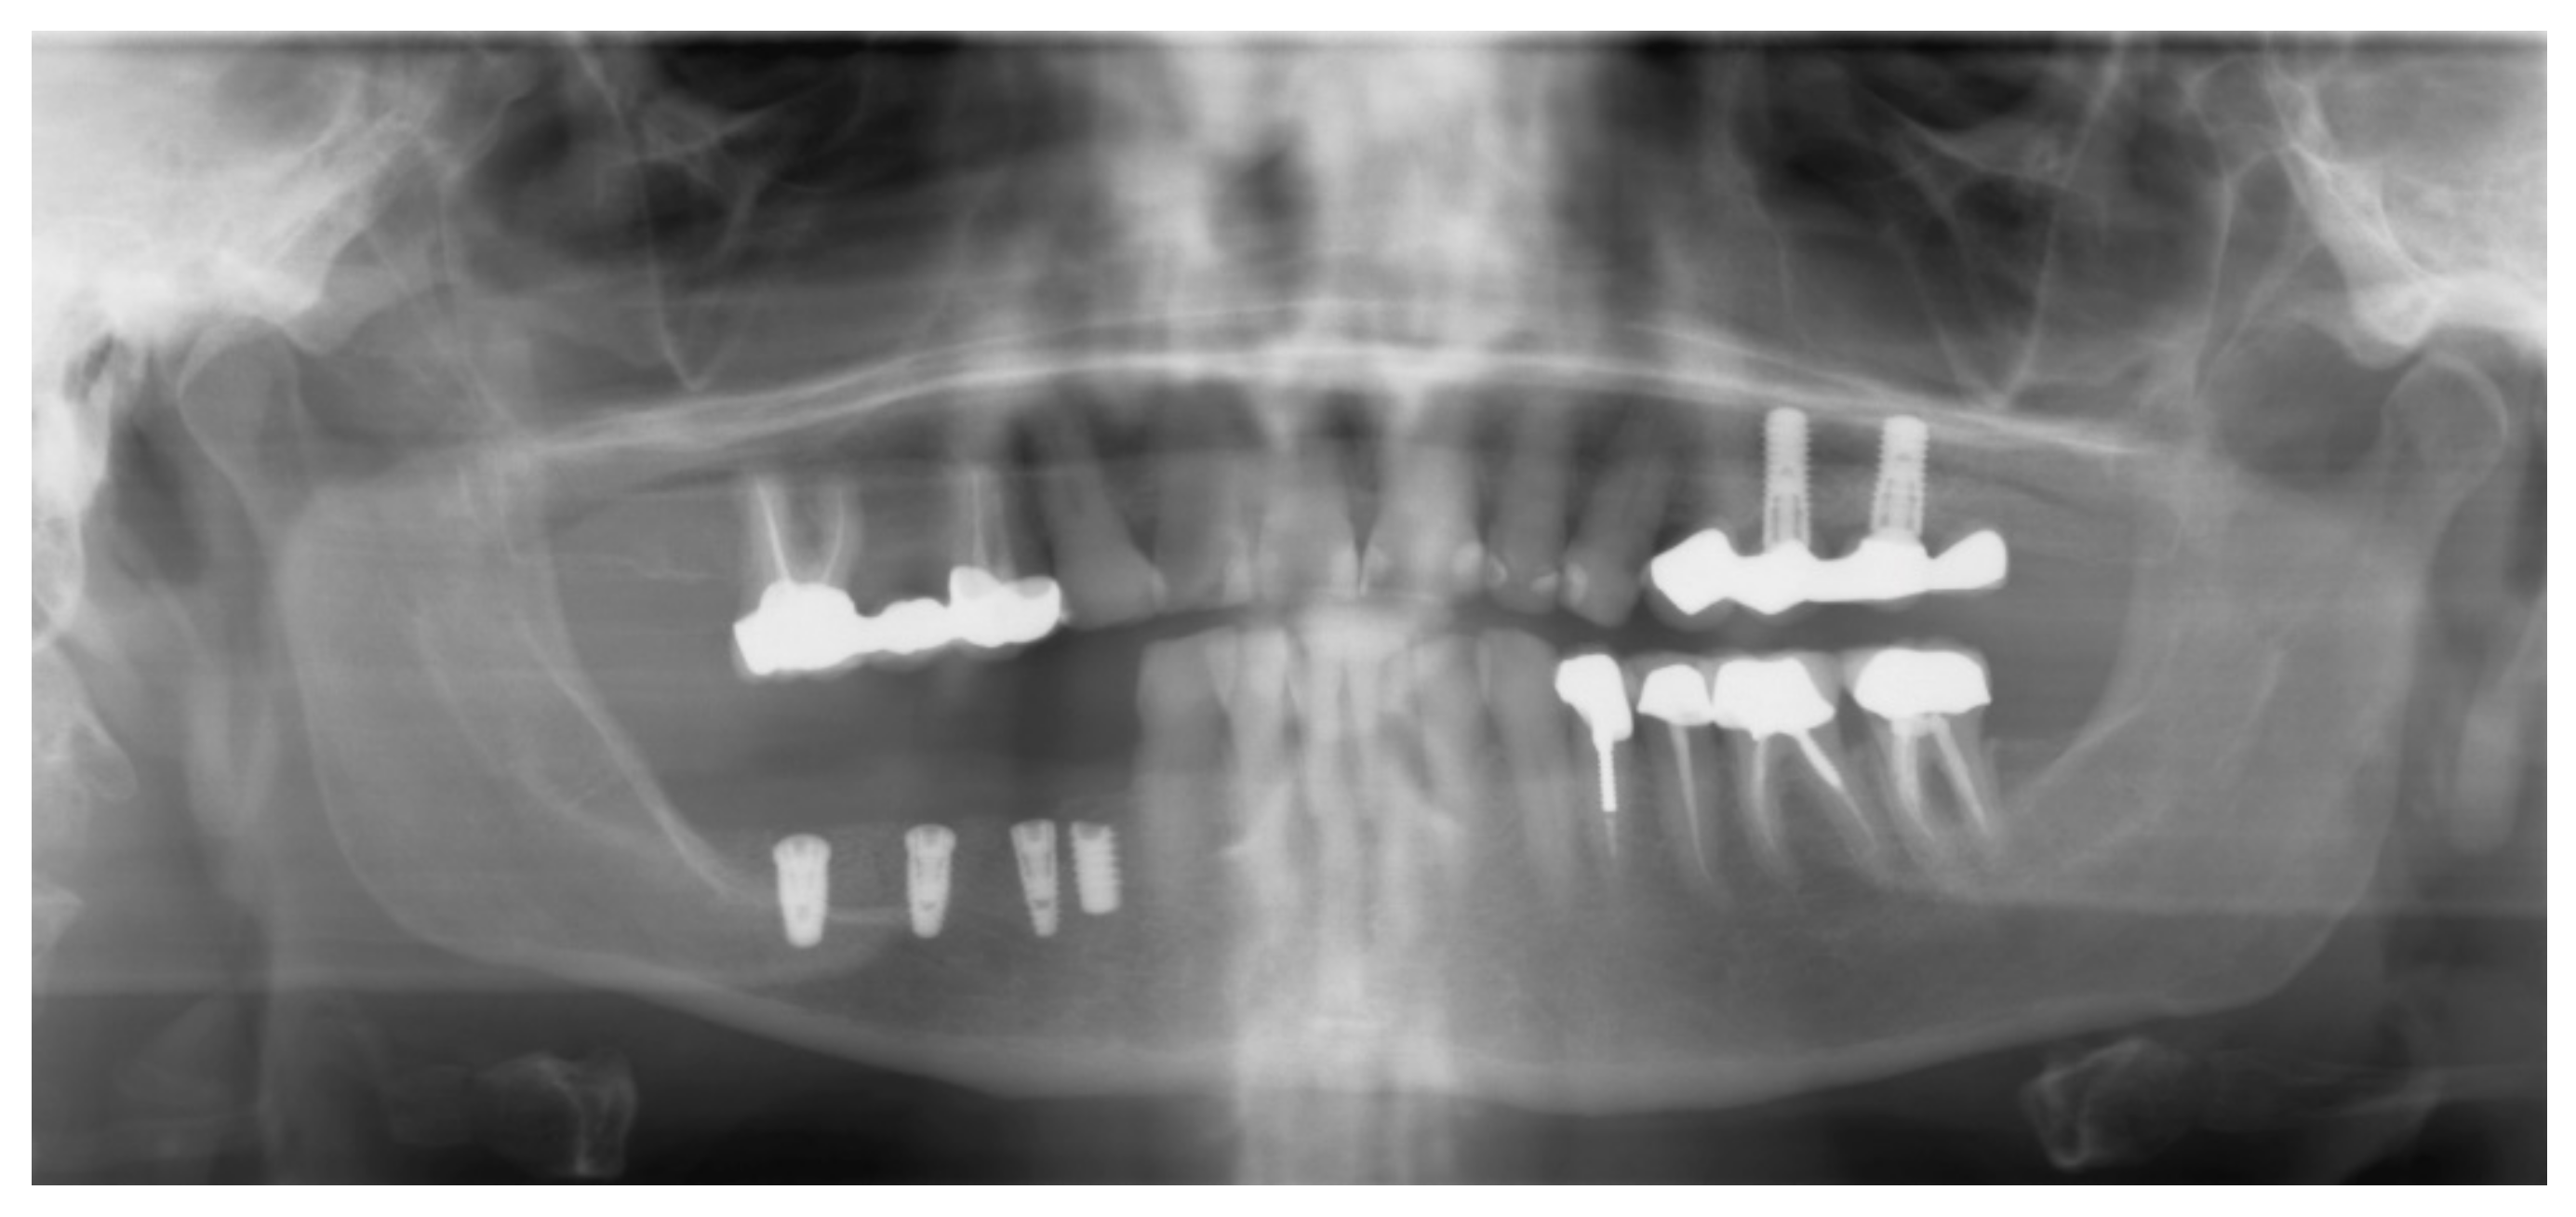

After 6 months of healing, a full-thickness flap was performed, and the screws to retain the ACBB were removed (Figure 14a,b). Three implants were placed with platform switching (Biomet 3i, T3 implants), according to the implant planning, using a surgical (prosthetic) guide. The implants were placed 1mm subcrestally, and a Puros Dermis® Allograft soft tissue matrix (Zimmer Biomet Dental) was placed over the implants to improve the thin tissue phenotype (Figure 15a,b and Figure 16).

Drill guide (a) and implants in place (b).

Figure 16.

Panoramic radiograph showing the implants in place.